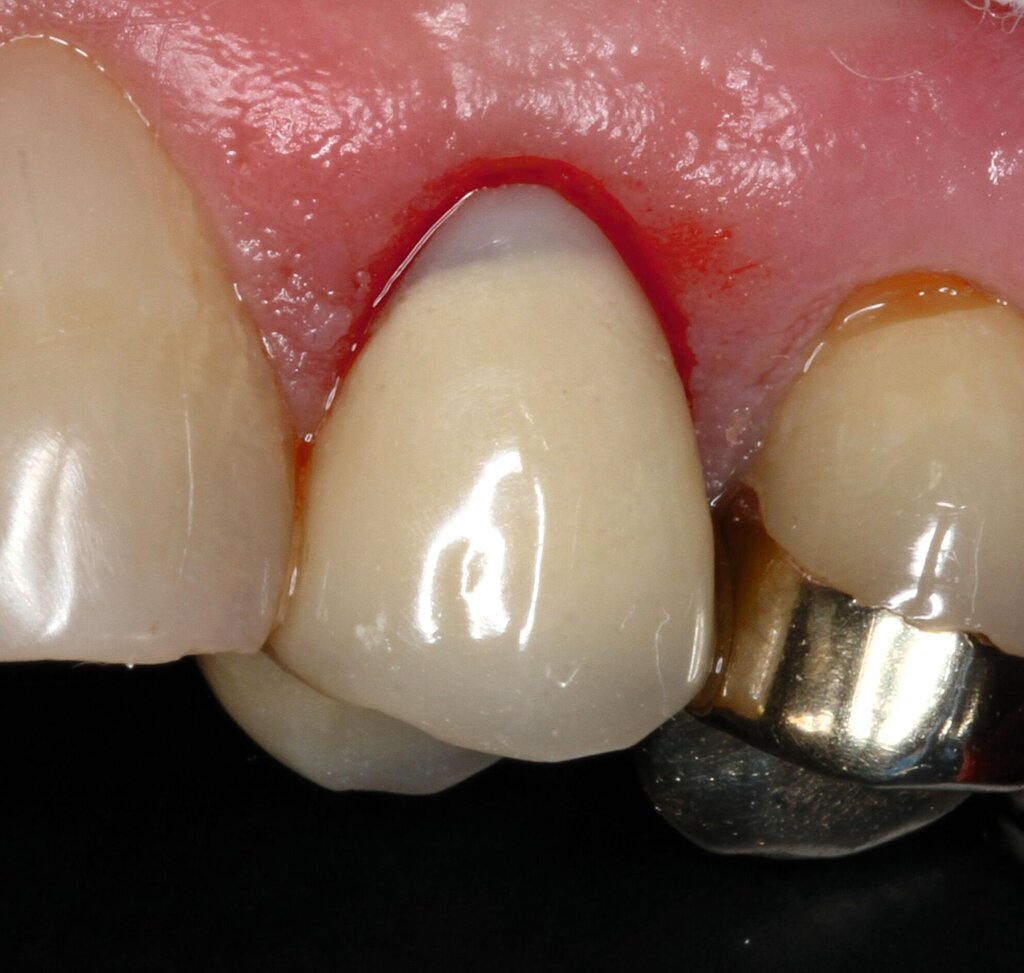

Vor 25 Jahren hatte der Patient ein Frontzahntrauma an Zahn 22 erlitten, der daraufhin mit einer Wurzelspitzenresektion und einer retrograden Amalgamfüllung versorgt worden war (Abbildung 3a). Dabei war die Zahnkrone mit einer keramisch verblendeten Stiftkrone aus Nichtedelmetall rekonstruiert worden, die nun aufgrund von Sekundärkaries insuffizient und gelockert war, jedoch keine Beschwerden verursachte. Klinisch wies der Zahn eine sehr kurze klinische Krone ohne ausreichendes Ferruledesign auf (Abbildung 5a) [Naumann et al., 2018a; Naumann et al., 2018b]. Neben dem Verdacht auf einen obliterierten mittleren Wurzelkanalabschnitt gab es röntgenologisch keinen Hinweis auf apikale Osteolysen oder parodontale Auffälligkeiten (Abbildung 3b). Der Patient entschied sich trotz des erhöhten Zahnhartsubstanzdefekts für den Zahnerhalt durch einen adhäsiv verankerten Kompositaufbau.

Für die restaurative Therapie von Zahn 22 wurde die alte Stiftkrone entfernt und die Stiftbohrung an die neue Indikation angepasst (Abbildungen 5a und 5b). Die Zahnkrone wurde dabei in drei Phasen wiederhergestellt: adhäsives Zementieren eines konfektionierten Glasfaserstifts, Stumpfaufbau und Modellation einer direkten Kompositkrone mit Silikonschlüssel, Frontzahnmatrize für komplexe Situationen und Schneepflugtechnik (Abbildungen 5c bis 5e) [Urkande et al., 2023; Amaro et al., 2021; Frese, 2020; Mannocci et al., 2002; Dimitrouli et al., 2011; Opdam et al., 2003]. Im Röntgenkontrollbild zeigt sich ein suffizienter Stiftaufbau (Abbildung 6).